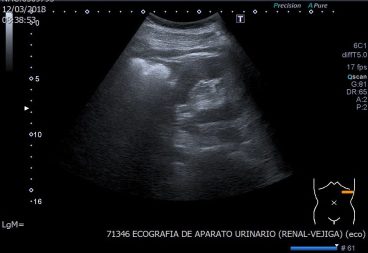

54. Protocolo de Abdomen. El Riñón Izquierdo.

Bien, después de haber estudiado el Bazo, continuamos el viaje anatómico ecográfico por el Riñón Izquierdo.

Ecográficamente ambos Riñones se comportan igual, lógico.

Cambian sin embargo algunas cosas en relación con la situación anatómica del Riñón Izquierdo, que está situado en el lado izquierdo y eso hace que esté más alto que el derecho, ya que el derecho se ve obligado a estar algo más distal debido al volumen que ocupa el Hígado.

Partiremos de la posición de Transverso para estudiar el Bazo en Transverso, así:

Observa el Pictograma en amarillo… una vez que tengas el Bazo así en la pantalla inicia un recorrido de bajada hacia distal y en la mayoría de las veces, a unos 4 ó 5 cms vas a encontrar el Riñón Izquierdo en Transverso, así:

Observa el Picto, y mira que apenas nos hemos movido de la zona, solo hemos bajado un poco. Encontramos un órgano como el que ves en la imagen, hipoecogénico en los bordes e hiper en el centro, es como una «C» abierta hacia la izquierda y hacia abajo. Cuando tengas esta imagen, pon tu sonda en longitudinal, vas a notar que te estás apoyando en el reborde costal izquierdo y que cuesta mantener el equilibrio, pero el objetivo es ver esta imagen:

En esta imagen ya puedes realizar la medida. Es el momento que te dediques a estudiar el órgano, haciendo movimientos de angulación de adelante hacia atrás en la imagen longitudinal y de arriba hacia abajo en la imagen en transverso. Ahora solo tienes que hacer la foto del Riñón en transverso, que la vimos antes, pero solo la usamos para localizar el órgano. Primero siempre la imagen en Longitudinal y luego la de Transverso.